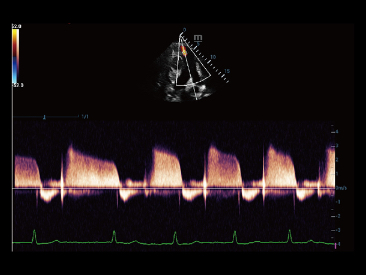

Adem├Īs de la calidad de imagen de primer nivel, Resona?7 tambi├®n mejora las capacidades de investigaci├│n cl├Łnica con el revolucionario V?Flow para la evaluaci├│n hemodin├Īmica vascular y con la adquisici├│n de planos m├Īs inteligente a partir de conjuntos de datos 3D para el diagn├│stico del SNC fetal. Al combinar el funcionamiento multit├Īctil basado en gestos m├Īs intuitivo y todas las caracter├Łsticas cl├Łnicas esenciales, Resona?7 realmente lidera las novedades en innovaci├│n de ecograf├Łas.